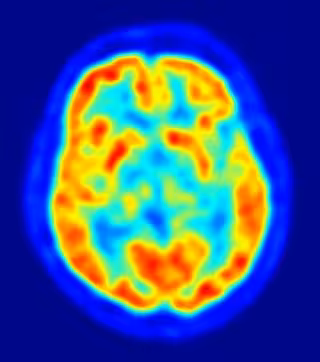

En el estudio, publicado en la revista 'PLoS Biology', el sentido de justicia de los individuos se desafiaba con un juego de justicia monetaria de dos jugadores y su actividad cerebral era medida de forma simultánea utilizando imágenes de resonancia magnética funcional (IRMf).

Investigaciones previas han sugerido que el área que controla la capacidad para analizar y realizar decisiones financieras se localiza en la corteza prefrontal y la ínsula. Utilizando las imágenes de IRMf, sin embargo, los investigadores vieron el área del cerebro que controla las decisiones financieras rápidas se localizaba en realidad en la amígdala, una parte evolutivamente muy antigua y primitiva del cerebro que controla sentimientos de ira y miedo.

Para explorar estos resultados en mayor profundidad, a los individuos se les proporcionaba el tranquilizante antiansiedad oxazepam o un placebo mientras jugaban. Los investigadores descubrieron que aquellos que recibían el fármaco mostraban una menor activación de la amígdala y una mayor tendencia a aceptar una distribución injusta del dinero, a pesar del hecho de que cuando se les preguntaba seguían considerando injusta la sugerencia.

En el grupo control, la tendencia a reaccionar de forma agresiva y a castigar al jugador que había sugerido la distribución injusta del dinero se vinculaba directamente con un aumento en la actividad en la amígdala. Se observó una diferencia de género, ya que los hombres respondían de forma más agresiva ante las sugerencias injustas que las mujeres al mostrar una mayor tasa de actividad de la amígdala. La diferencia de género no se descubrió en el grupo que recibió el fármaco oxazepam.